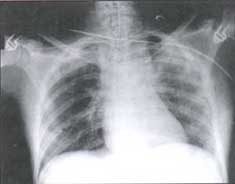

Figura No. 4 Paciente de 30 años, atropellada por un automóvil.

Radiografía inicial AP, muestra discreto ensanchamiento mediastinal. Hay fracturas costales izquierdas y contusión pulmonar.